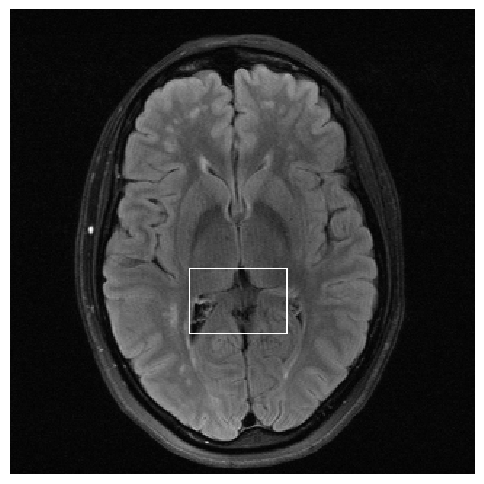

Figure 3: Reconstructions results. Rows 1 and 3: Examples of comparing the ground truth (GT) fully sampled image to the reconstructed images obtained by the three models (1-3), NPB-REC, baseline, E2E-VarNet trained with Dropout, and the NPB-REC std. map at accelerations R=4𝑅4R=4, R=8𝑅8R=8, respectively. Rows 2 and 4: The corresponding annotated ROIS of Nonspecific white matter lesions.

Fig. 3 presents examples of reconstruction results obtained by (1) our NPB-REC approach, (2) the baseline, and (3) Monte Carlo Dropout, for equispaced masks with two different acceleration rates R=4𝑅4R=4 and R=8𝑅8R=8. The reconstructed images predicted by the three models are smoother than the reference image. This is due to the fact that all the models were trained with SSIM loss, which tends to produce overly smooth reconstructions while preserving the diagnostic content and the anatomical features Sriram et al. (2020a). These images can be enhanced by dithering the image by adding a small amount of random Gaussian noise to produce a more textured reconstruction, as proposed in Sriram et al. (2020b).

Table 1 presents the mean PSNR and SSIM metrics, calculated over the whole inference set, for the three models. Our NPB-REC approach achieved significant improvements over the other methods in terms of PSNR and SSIM (Wilcoxon signed-rank test, pmuch-less-than\ll1e-4, except for SSIM values in line W, R=4𝑅4R=4 where they are roughly the same for NPB-REC and Baseline). The improvement in the reconstruction performance can be noted both quantitatively from the metrics, especially for masks with acceleration rate R=8𝑅8R=8, and qualitatively via the images of annotations, where our results show less smoothness than those obtained by Dropout.